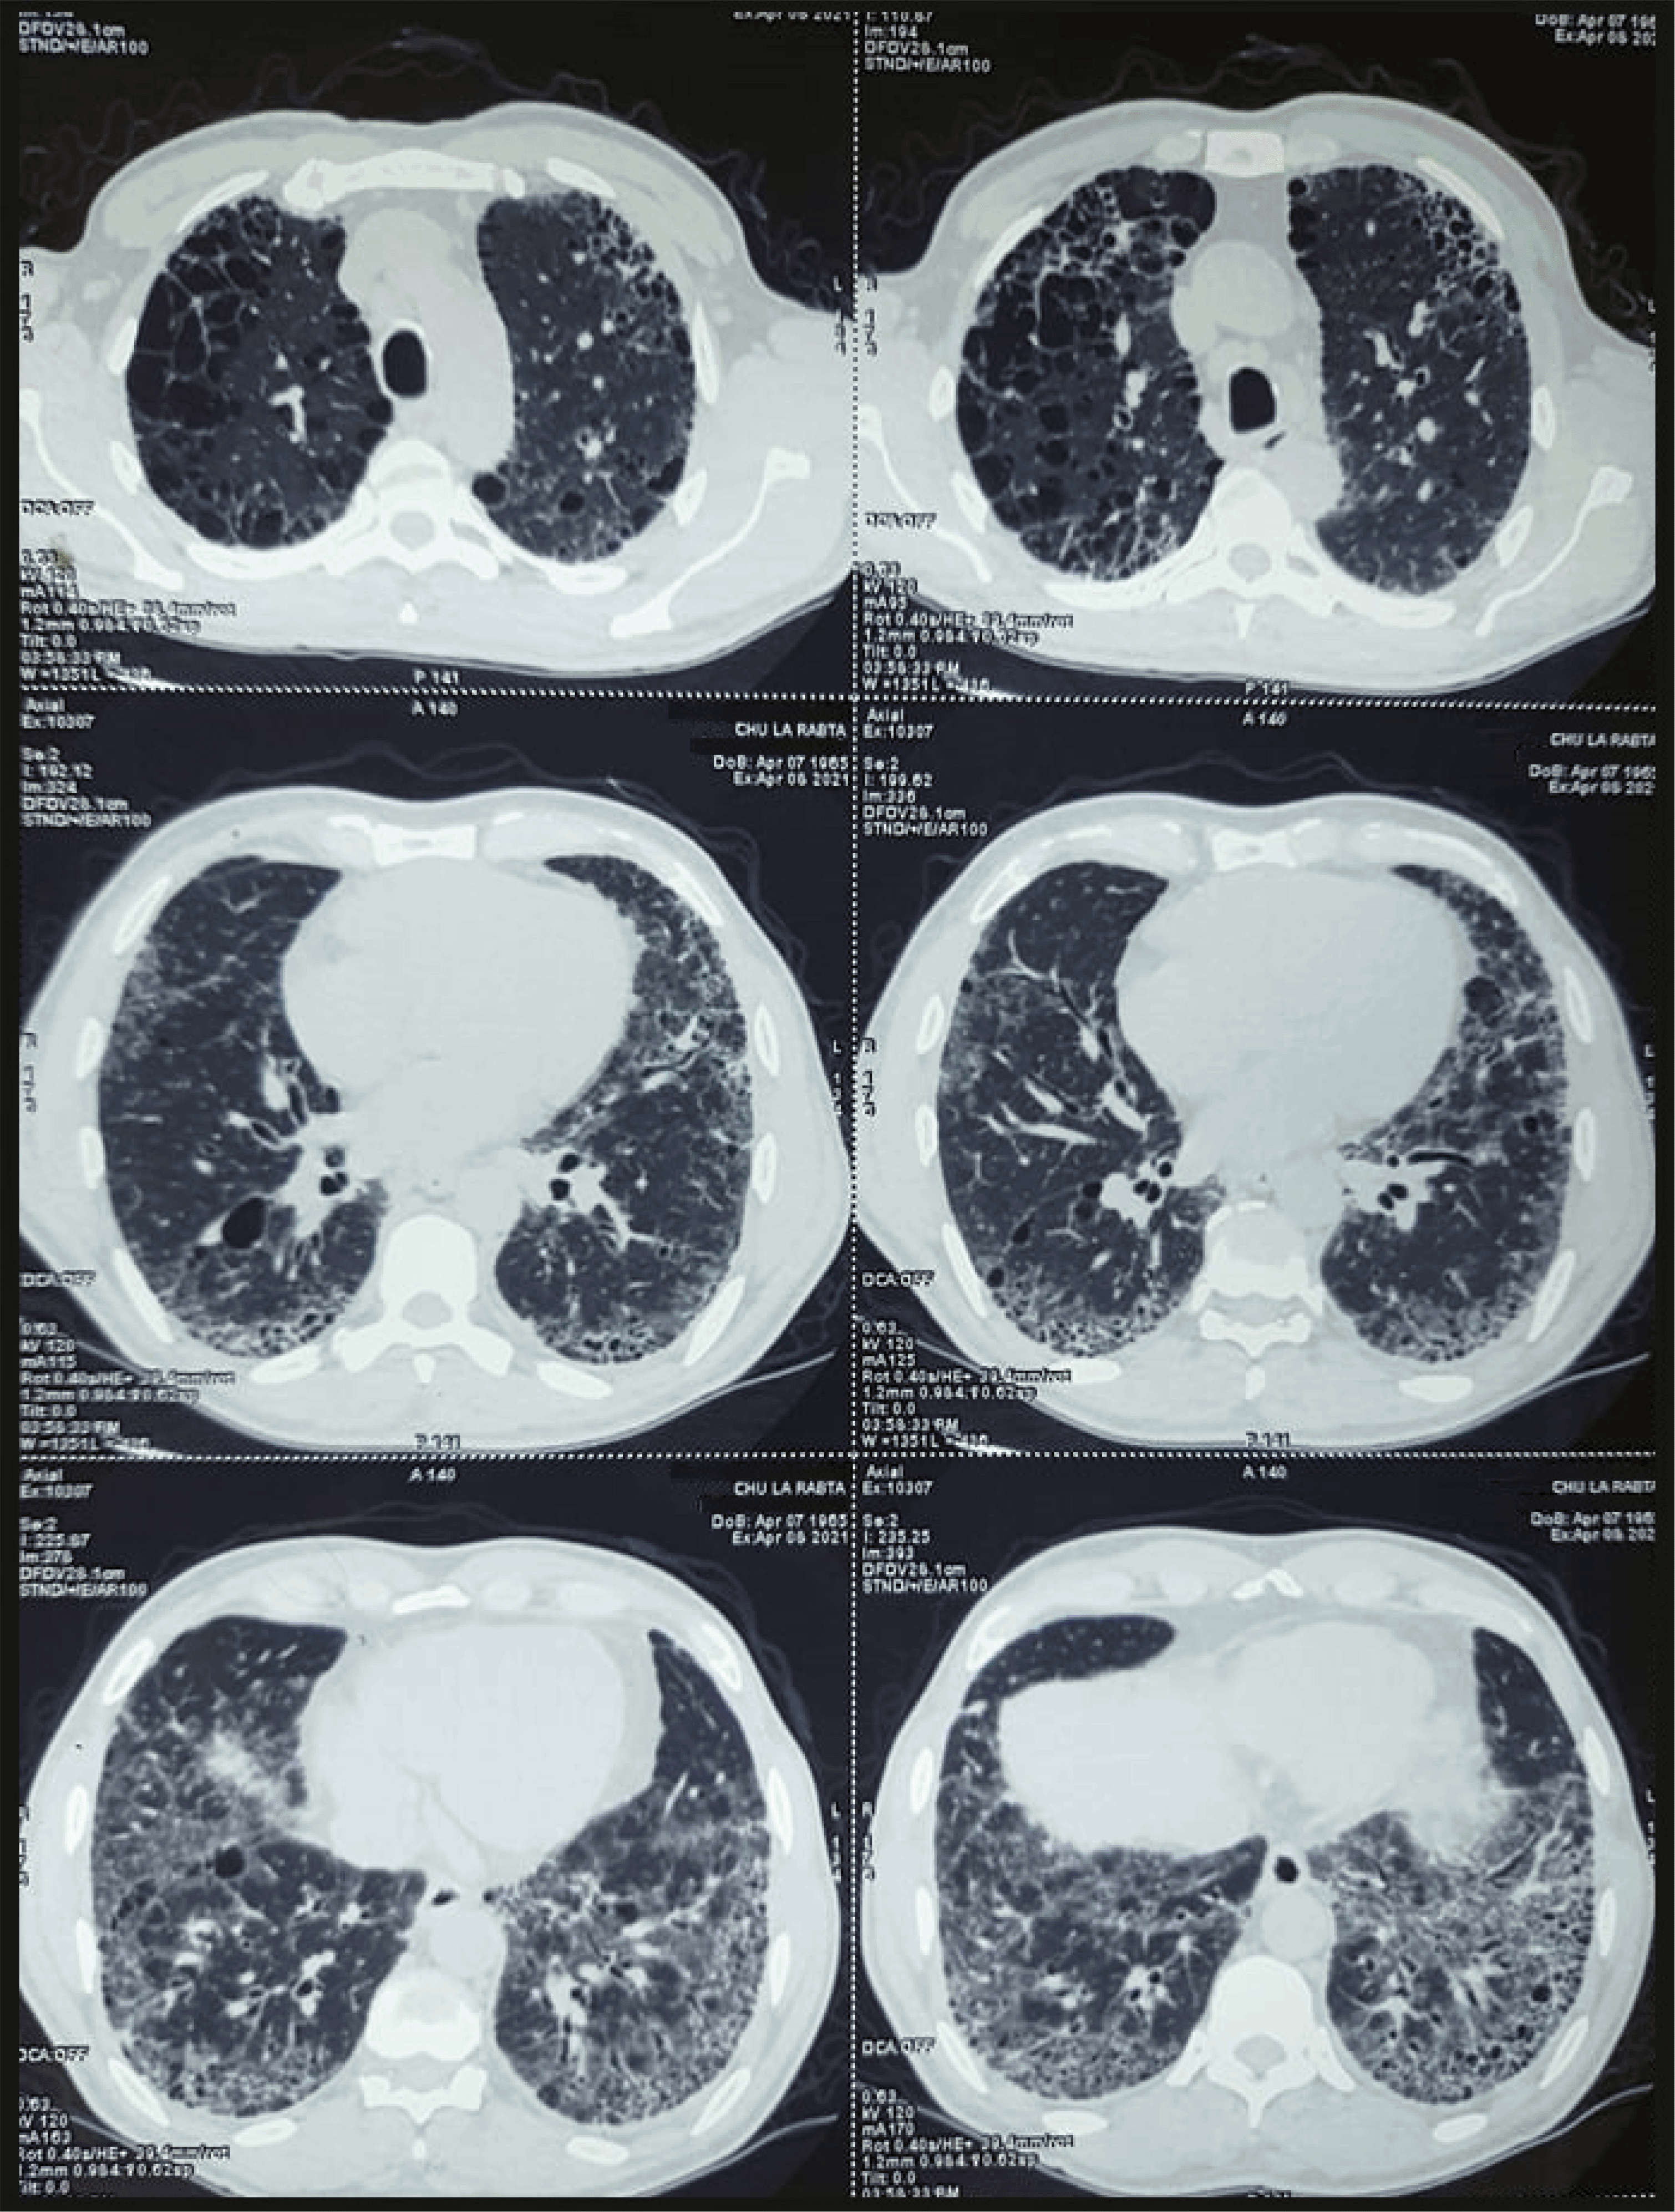

Chest tomography was performed and it revealed fibrosing diffuse interstitial lung disease consisting of bilateral septal thickening, ground-glass opacities and a honeycomb pattern. These aspects predominated at the two bases and on the periphery (Figure 2).

Because of occupational history of chronic crystalline silica exposure, characteristic radiologic findings and clinical signs, the diagnosis of silicosis was given.